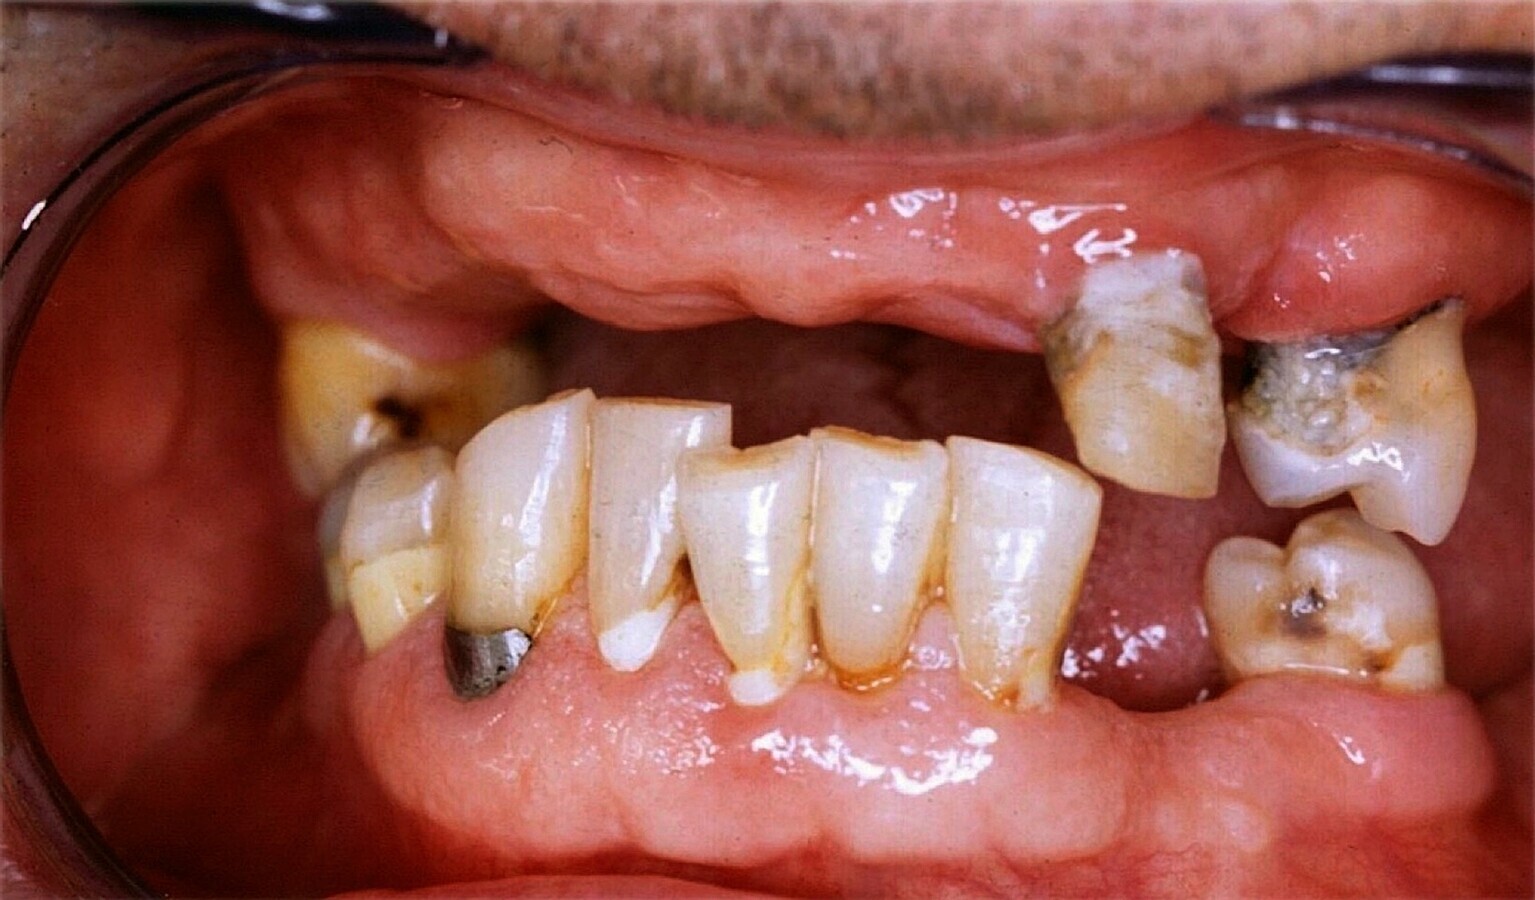

Figura 4. Paciente de alto riesgo, con ausencias dentales, portador de prótesis removible, obturaciones, caries activas y presencia de placa. En casos de alto riesgo se deben realizar los tratamientos pertinentes y las revisiones cada 2 a 3 meses.